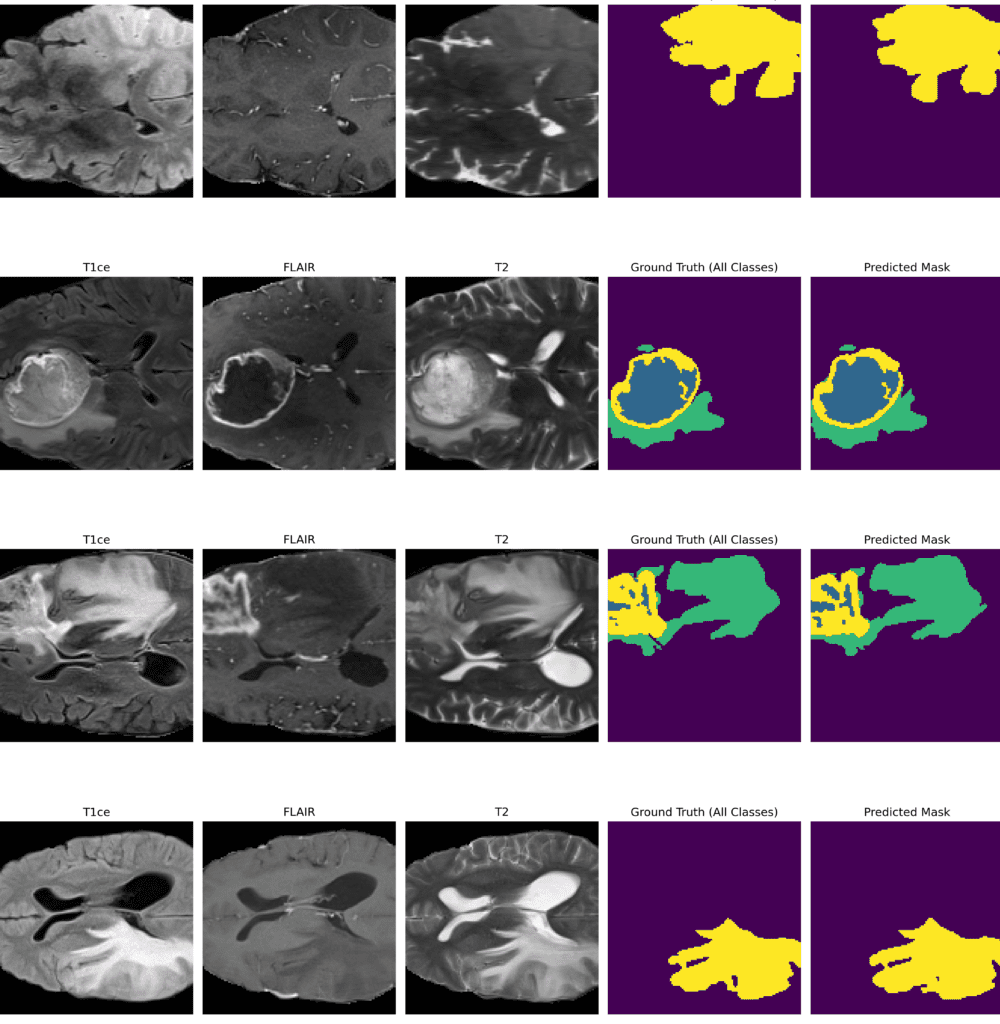

• 🧬 Multi-Modal MRI Fusion: Supports FLAIR, T1, T1CE, and T2 modalities for comprehensive tumor representation.

Multimodal MRI Inputs

Fusion of FLAIR/T1/T1CE/T2 modalities to capture complementary tumor signals.

Segmentation Outputs

Predicted tumor subregions (WT/TC/ET) with strong boundary delineation on BraTS samples.